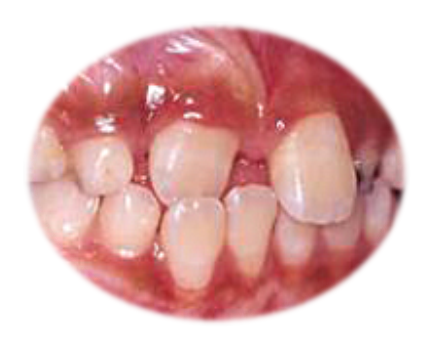

Nicanje gornjih stalnih zuba iza donjih se stručno naziva “ukršteni zagrižaj”(Slika 3.) i ako se na vreme otkrije(pre nego što gornji zubi u potpunosti izniknu i postave se iza donjih), sa jednostavnim vežbama može da se spreči kasnije nošenje apartata za ispravljanje zuba.

Slika 2. Ukršteno nicanje gornjih sekutića iza donjih

Slično se može očekivati ako se stalni gornji zubi pojavljuju iza mlečnih(Slika 3.). Ponekada se dešava da posle povreda ili infekcije, korenovi mlečnhi zubi srastaju sa kosti(stručno se zove ankiloza), ne dolazi do njihovog topljenja, pa su stalni sekutići primorani da izlaze sa unutrašnje strane. To ih isto može dovesti u gore spomenuti ukršteni zagrižaj.

Slika 3. Nepravilno nicanje gornjih sekutića iza mlečnih zuba koji nisu počeli da se tope.